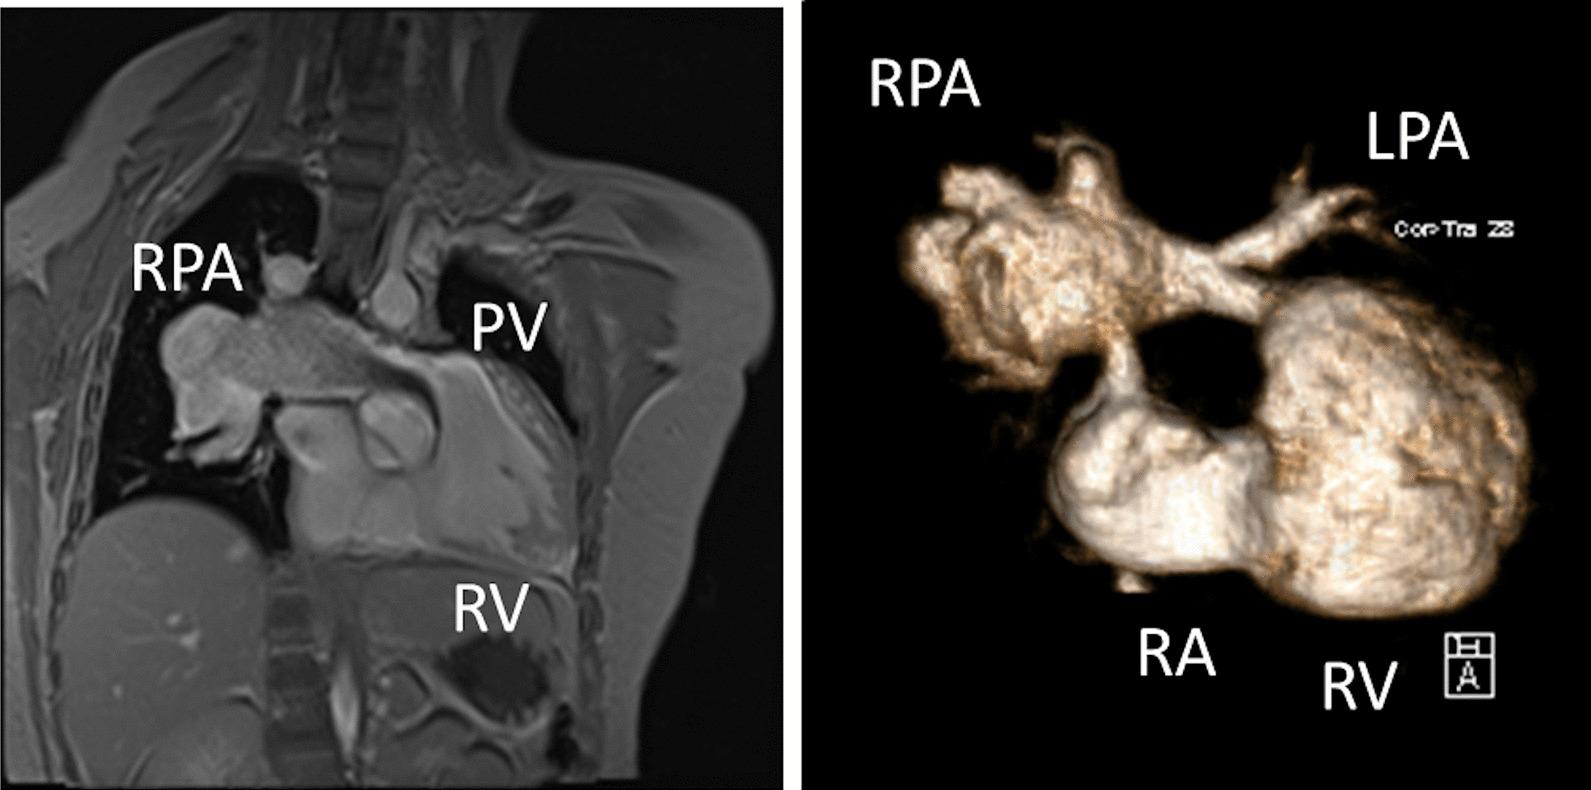

Cardiovascular magnetic resonance (CMR) has been utilized in the management and care of pediatric patients for nearly 40 years. It has evolved to become an invaluable tool in the assessment of the littlest of hearts for diagnosis, pre-interventional management and follow-up care. Although mentioned in a number of consensus and guidelines documents, an up-to-date, large, stand-alone guidance work for the use of CMR in pediatric congenital 36 and acquired 35 heart disease endorsed by numerous Societies involved in the care of these children is lacking. This guidelines document outlines the use of CMR in this patient population for a significant number of heart lesions in this age group and although admittedly, is not an exhaustive treatment, it does deal with an expansive list of many common clinical issues encountered in daily practice.

心血管磁共振(CMR)在儿科患者的管理和护理中已经应用了近 40 年。它已经发展成为评估最小的心脏的宝贵工具,用于诊断、介入前管理和随访。尽管在许多共识和指南文件中提到,但在儿科先天性心脏病和后天性心脏病领域,目前还缺乏一份由众多参与儿童护理的学会共同认可的、最新的、独立的、针对 CMR 使用的大型指南。本指南文件概述了 CMR 在该年龄段的许多心脏病变中的应用,尽管不能说是详尽的治疗方法,但它确实涉及了在日常实践中经常遇到的许多常见临床问题的广泛列表。